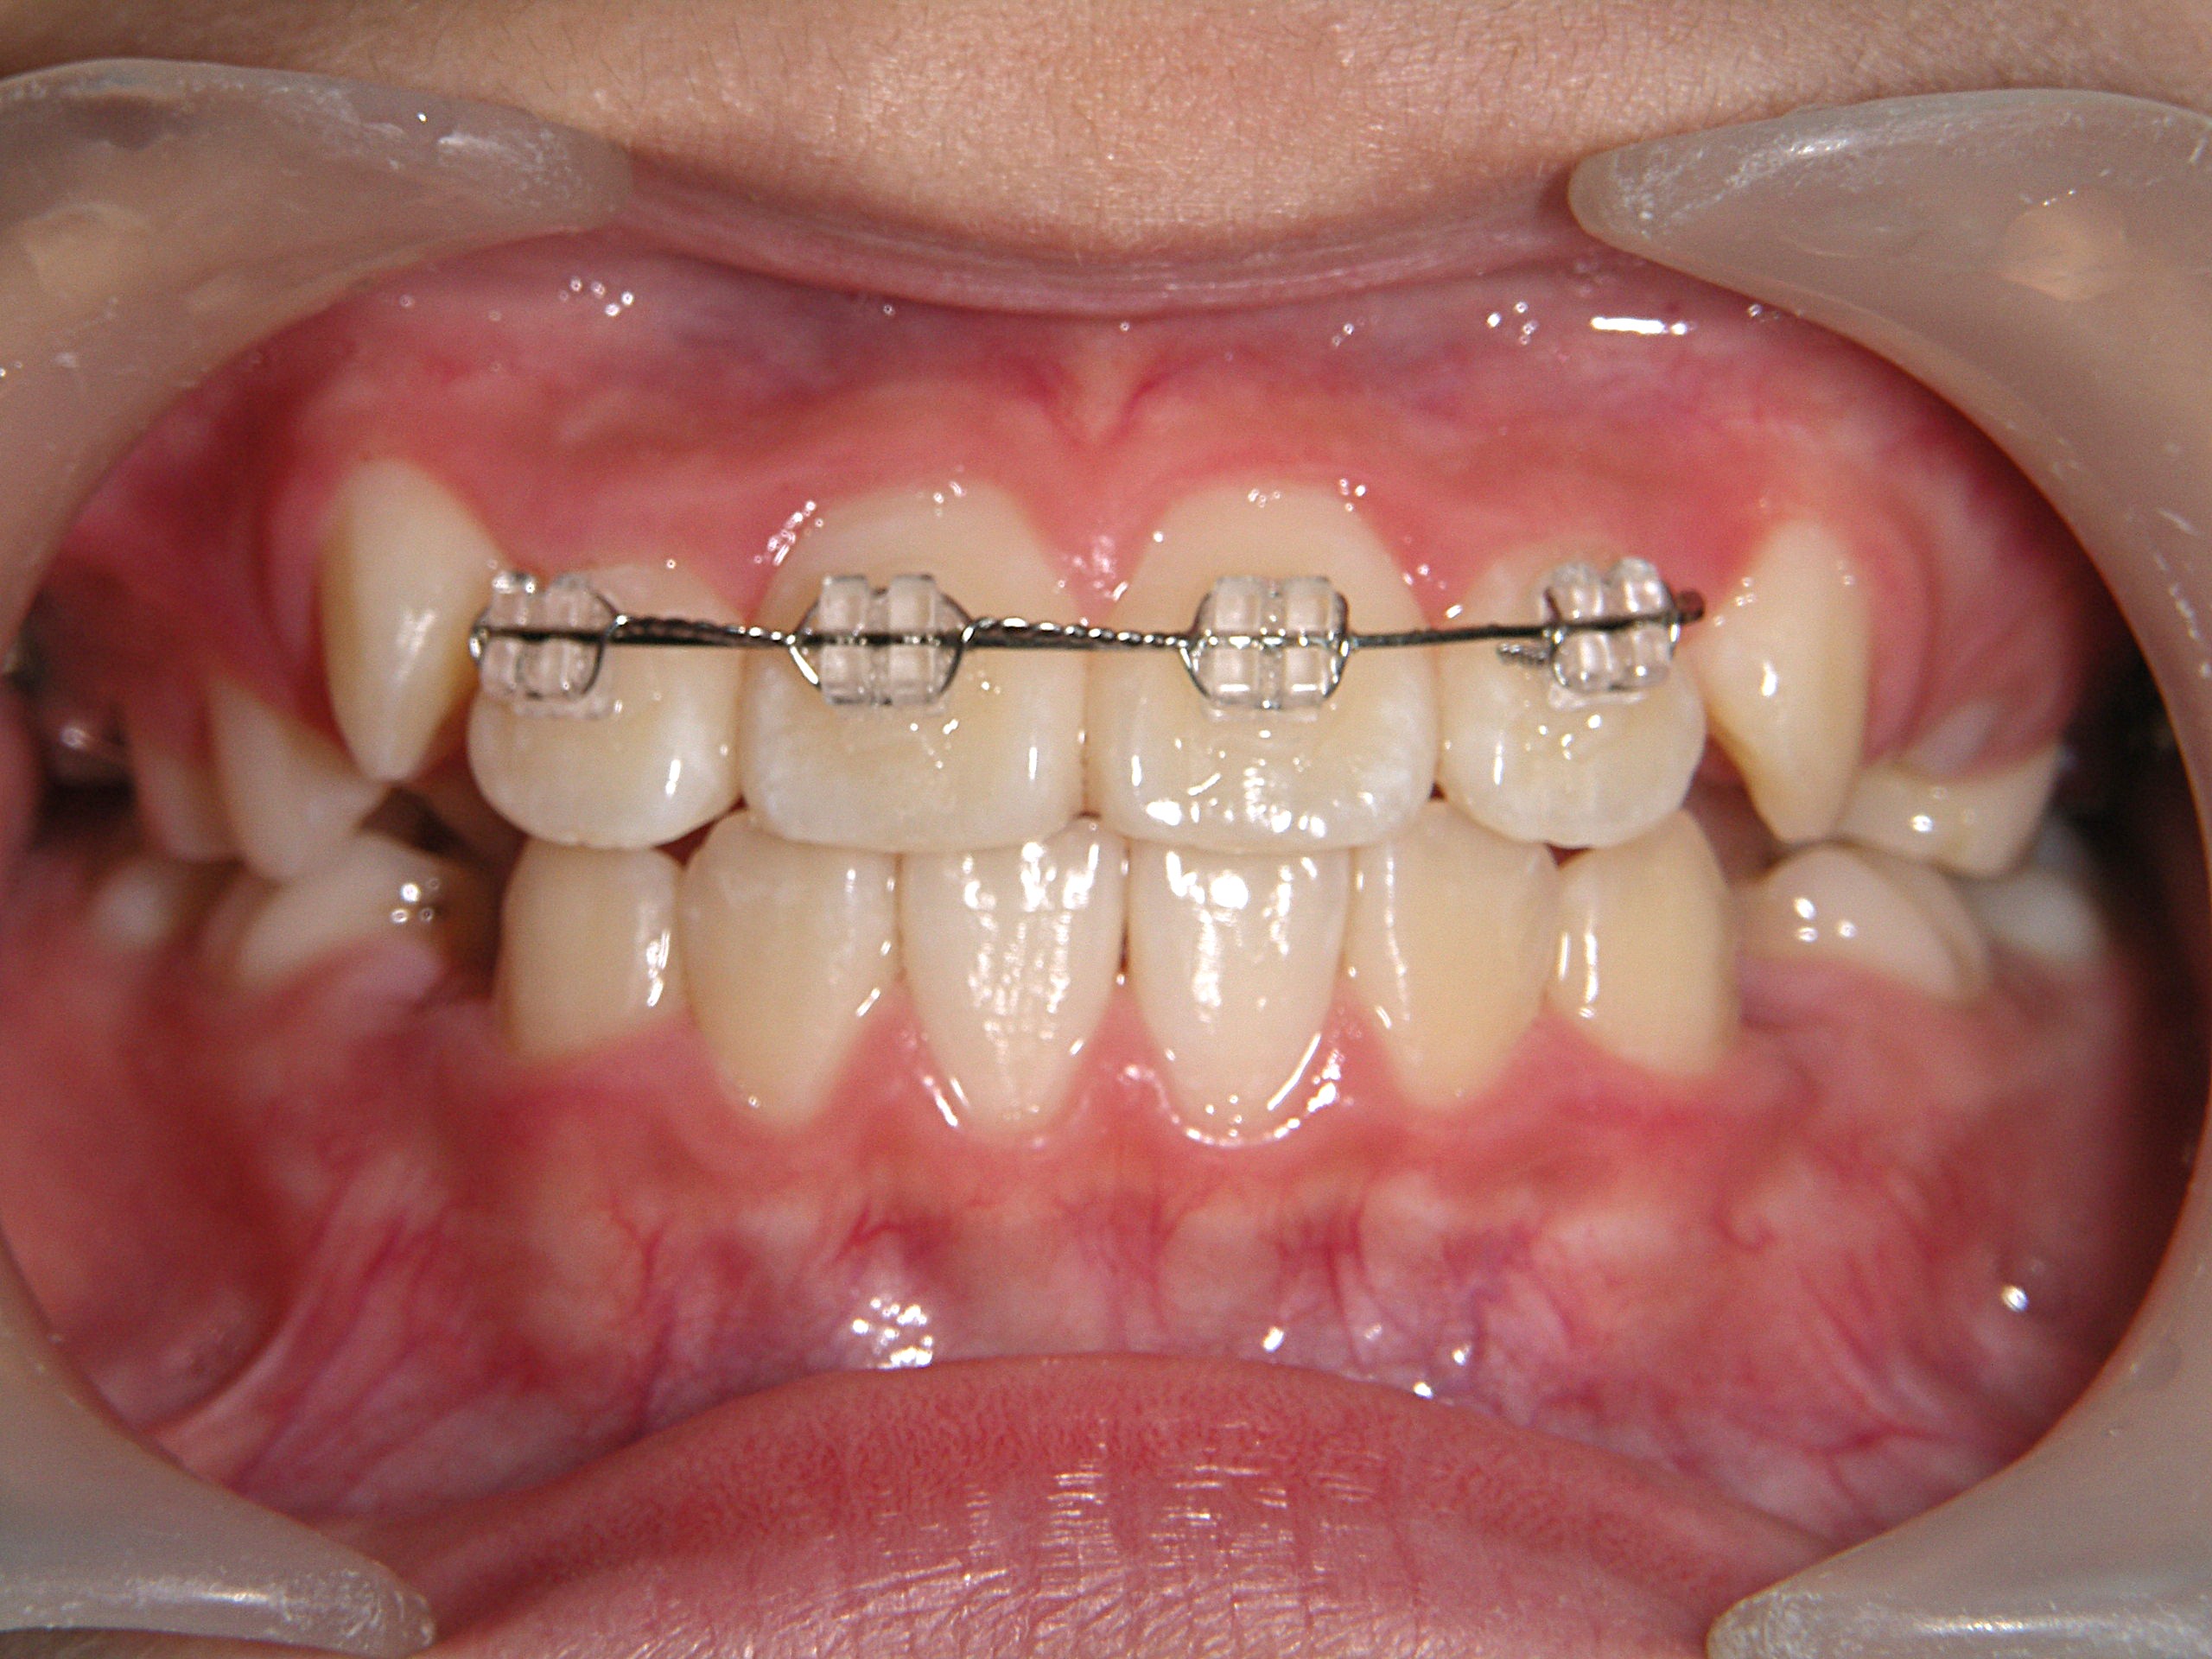

第1期治療開始時

口腔内写真

年齢

9歳 男性

主訴(患者様のお悩み)

歯のデコボコを治したい

診断

上顎前歯部叢生(上の前歯のデコボコ)

上下顎側切歯クロスバイト(部分受け口)

上顎狭窄歯列(上のあごが小さめ)

歯冠幅径大(歯が大きめ)

治療方針

上顎緩徐拡大(上あごを拡大)

上の前歯部のみワイヤー矯正

使用装置

緩徐拡大装置(クワドヘリックス)

前歯部ブラケット

治療期間の目安:約半年~1年(保定期間を除いた期間)